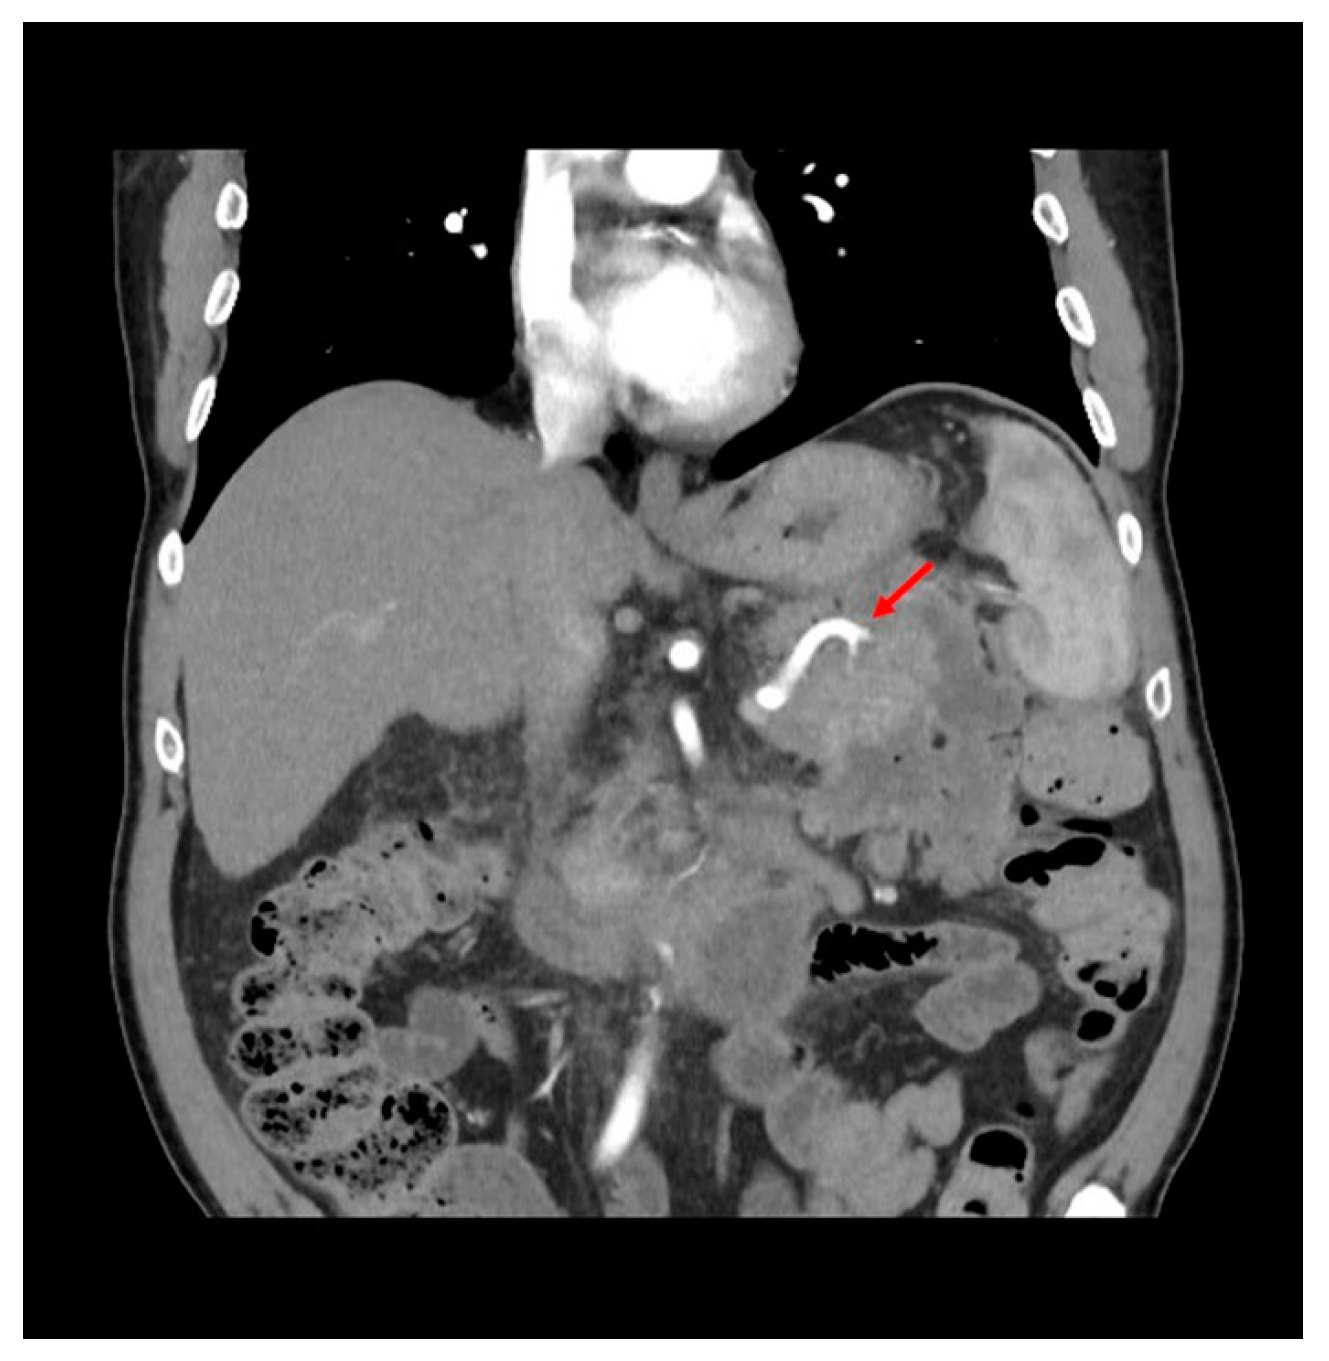

2. Case Presentation